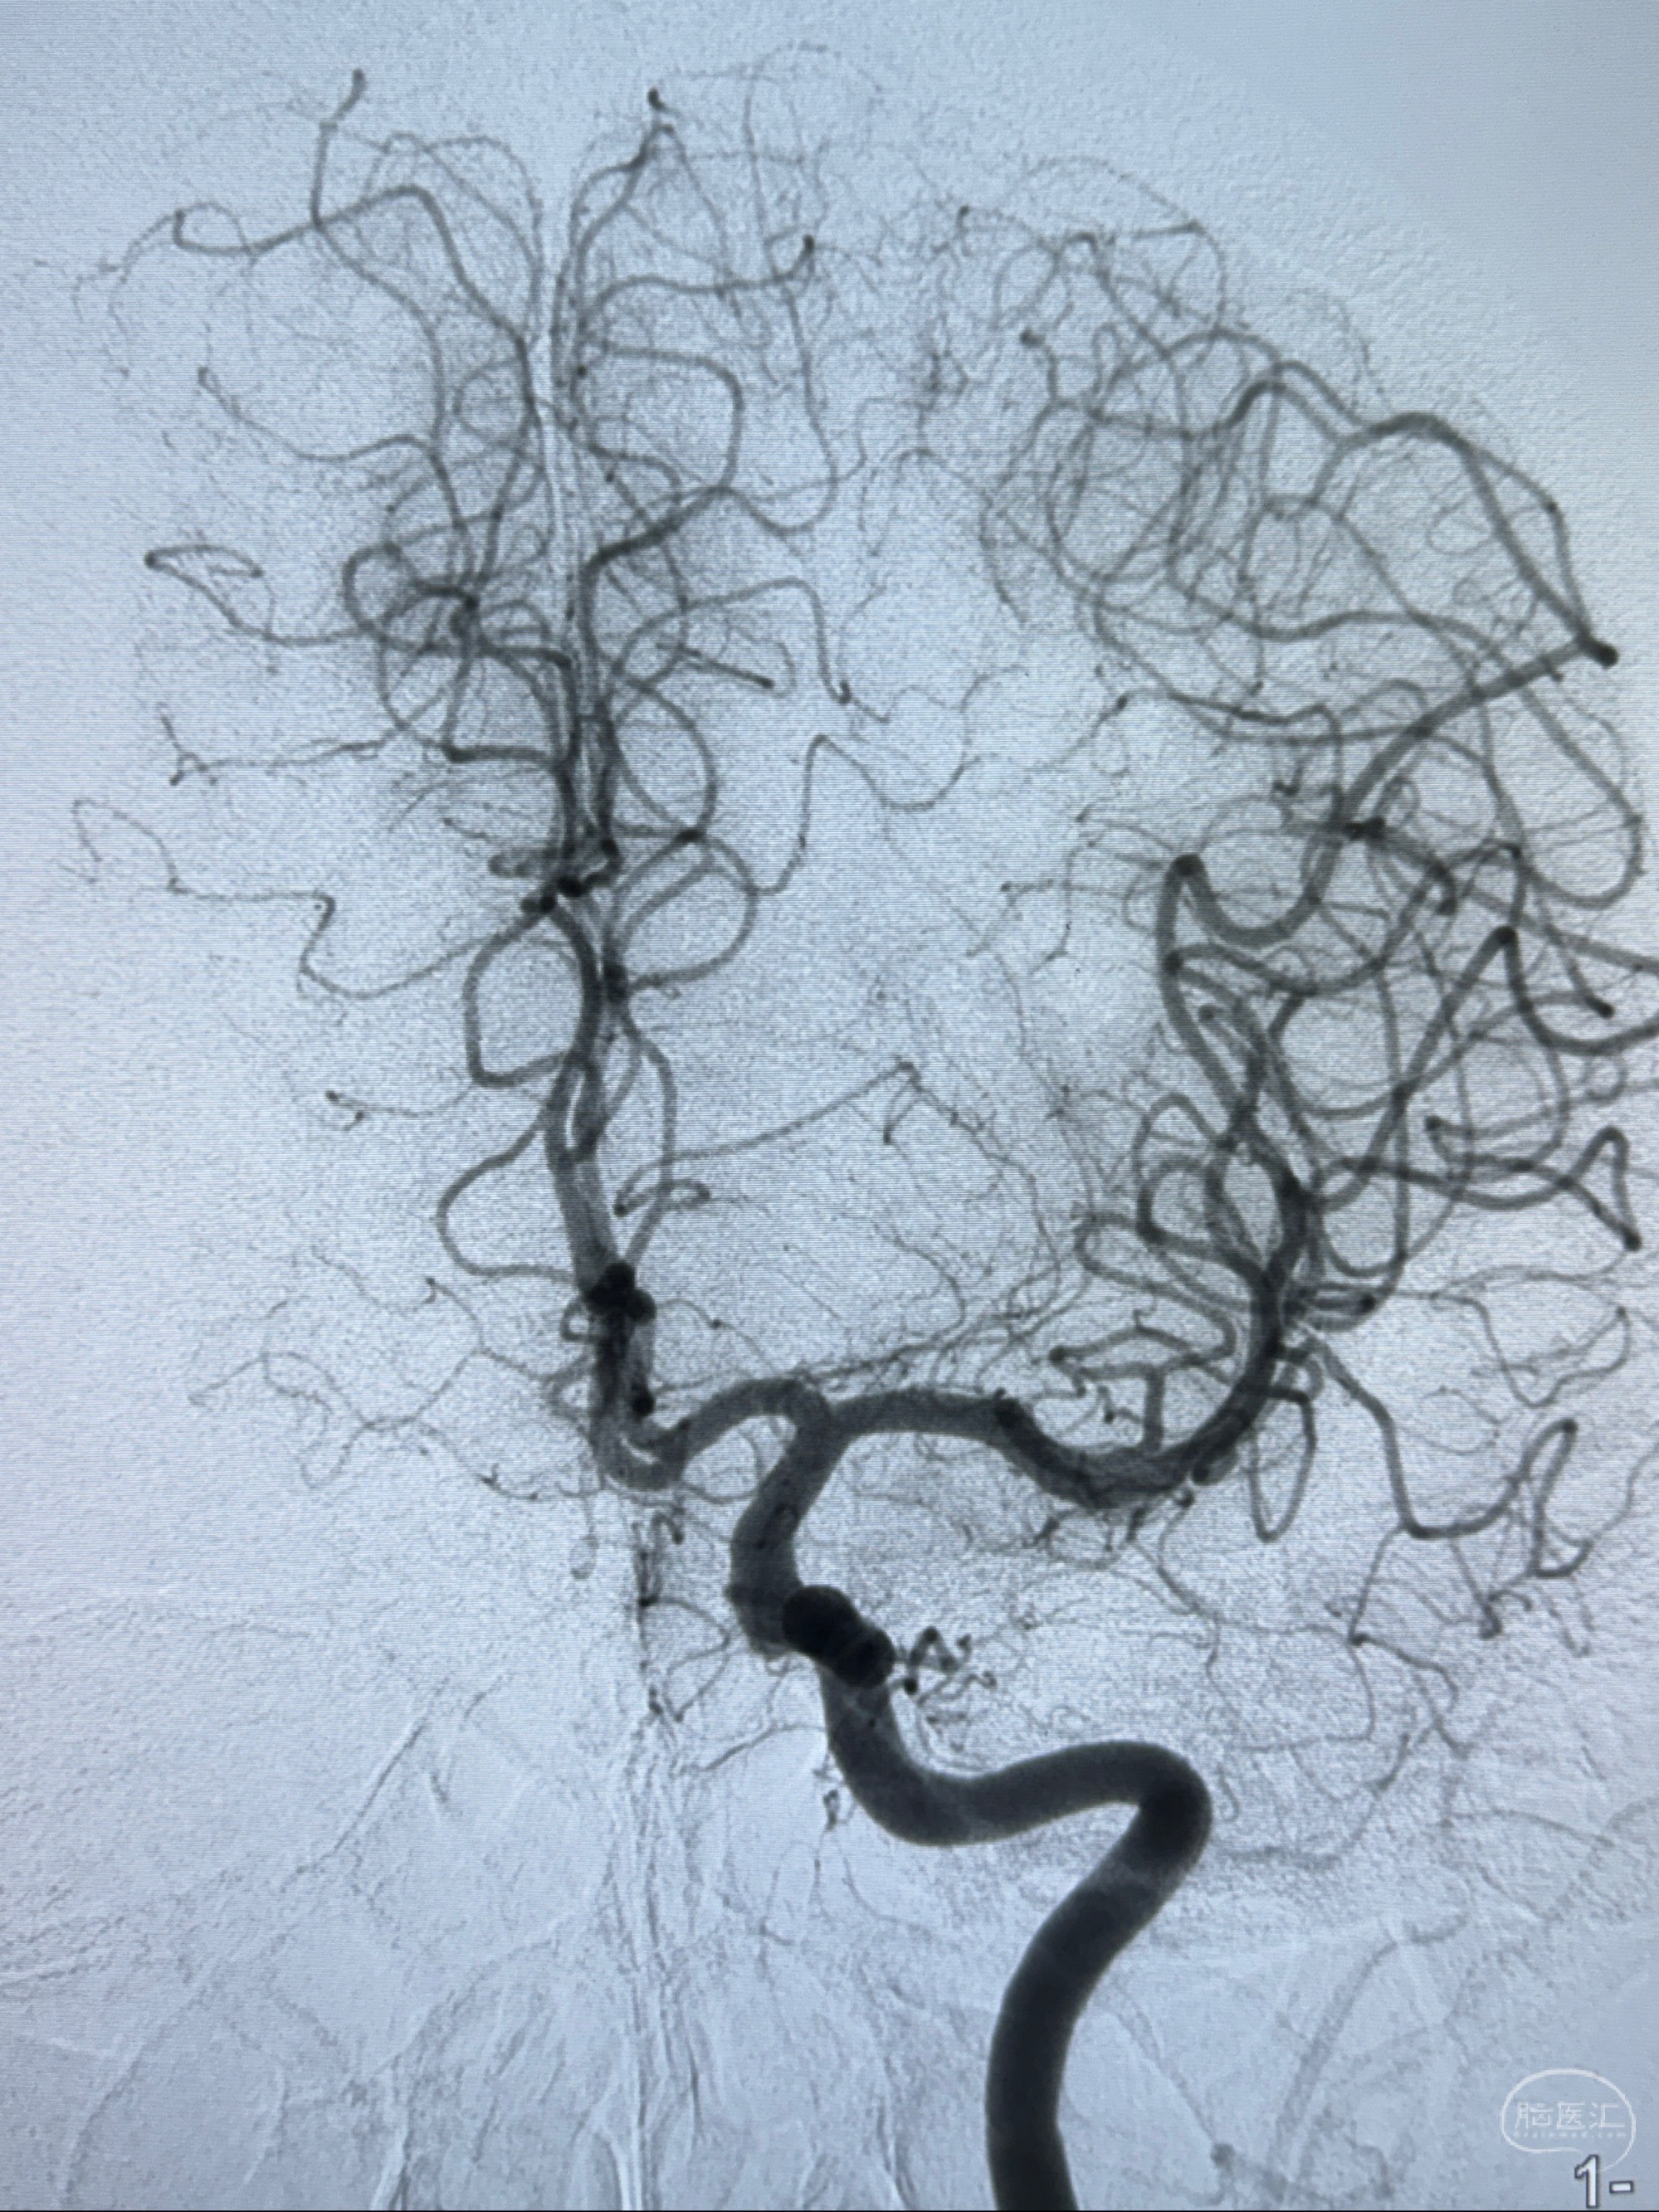

2023-11-01 蓝十字脑科医院 头颅MRI+DWI+MRA:左侧枕叶皮层下小斑片缺血或变性灶,右侧大脑前动脉A1段毛糙,显影淡、纤细,建议完善CTA;

2023-11-03 蓝十字脑科医院 头颅CTA:左侧颈内动脉C6段微小动脉瘤可能(约2mm),右侧大脑前动脉A1段纤细(对侧优势),左侧大脑中动脉提前分叉。

1.左侧颈内动脉瘤

- 随访?

- 支架辅助治疗?